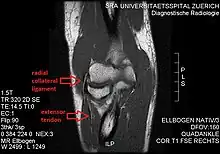

Radial collateral ligament of elbow joint

The radial collateral ligament (RCL), lateral collateral ligament (LCL), or external lateral ligament[Explain 1] is a ligament in the elbow on the side of the radius.